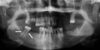

Impacted tooth visible on X-ray – diagnosis?

• Dens inclusus (impacted tooth).

• Treatment: Surgical extraction

Partially erupted tooth with recurrent infection – diagnosis?

• Dens semi-inclusus cum pericoronitide

• (partially erupted tooth with pericoronitis).

• Treatment: Extraction